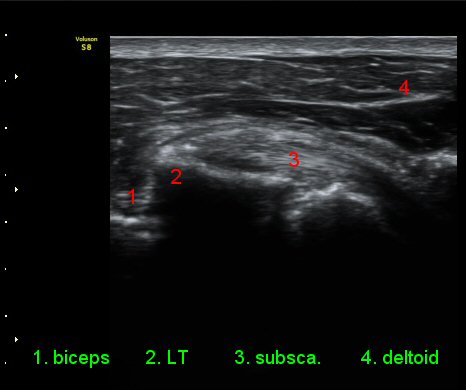

ÃÊÀ½ÆÄ °Ë»ç

ŽÃÊÀÚ¸¦ ¾à°£ ´Ù¸®ÂÊ, ³»ÃøÀ¸·Î À̵¿ÇÏ´Ï °ß°©ÇÏ±Ù°Ç Ç¥Ãþ¿¡ ¸¹Àº ¾çÀÇ ¼ö¾×Àú·ù°¡ °üÂûµÈ´Ù(»çÁø 3).

ÆÈÀ» ¿ÜȸÀüÇÏ´Ï °ß°©ÇÏ±Ù°Ç Ç¥ÃþÀÇ ¼ö¾×Àú·ù°¡ ´õ¿í È®½ÇÇÏ°Ô °üÂûµµ´Ï´Ù(»çÁø 4).